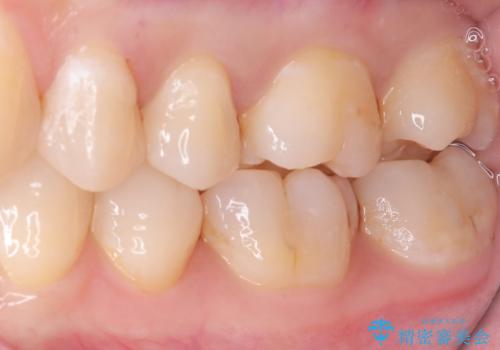

- 主訴:左上真ん中らへんの歯が欠けてしみるので治したい

審美性、適合性の良いセラミックインレーでのやり替えとなりました。

左上4近心に実質欠損を認め、遠心から咬合面にかけてはCR修復が施されていたため、MODインレー窩洞としました。